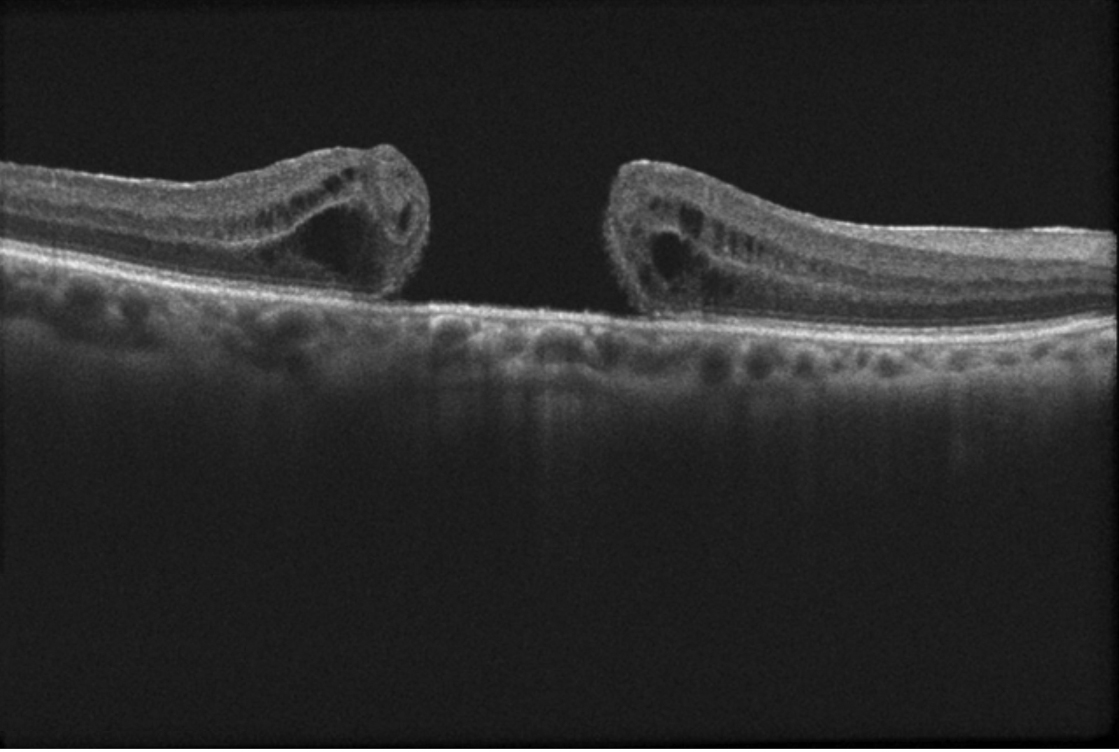

OCT Buraco Macular

OCT

Buraco Macular

Defeito de espessura total na fóvea central. Causa distorção visual significativa e redução da acuidade visual central.

Diagnóstico OCT

Vitrectomia + Peeling

95% Sucesso